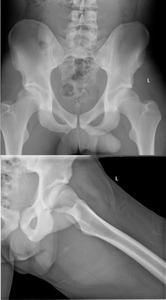

The on-field medical team transported the subject to a nearby emergency room where plain film radiographs revealed a posterior left hip dislocation (Figures 1A-B), negative for fracture, along with mild pre-existing femoral head CAM deformities bilaterally, thus, the diagnosis was consistent with a type 1 dislocation.

The left hip was reduced (Figures 2A-B) and the subject was instructed to be non-weight-bearing on the left lower extremity with bilateral axillary crutches for two weeks, followed by adding 25% weightbearing each week thereafter to weight bearing as tolerated while maintaining standard posterior hip precautions (no hip flexion greater than 90°, no hip adduction, no hip internal rotation) for a total of six weeks. Magnetic resonance imaging was also performed of the left knee and findings indicated a “low grade” left medial collateral ligament sprain.